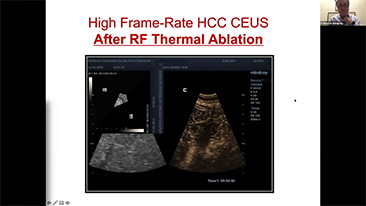

General Imaging

Mindray Resona General Imaging solutions help clinicians realize more accurate and efficient diagnosis and treatment results through comprehensive subdivision application probes and efficient clinical application tools.

General Imaging Products